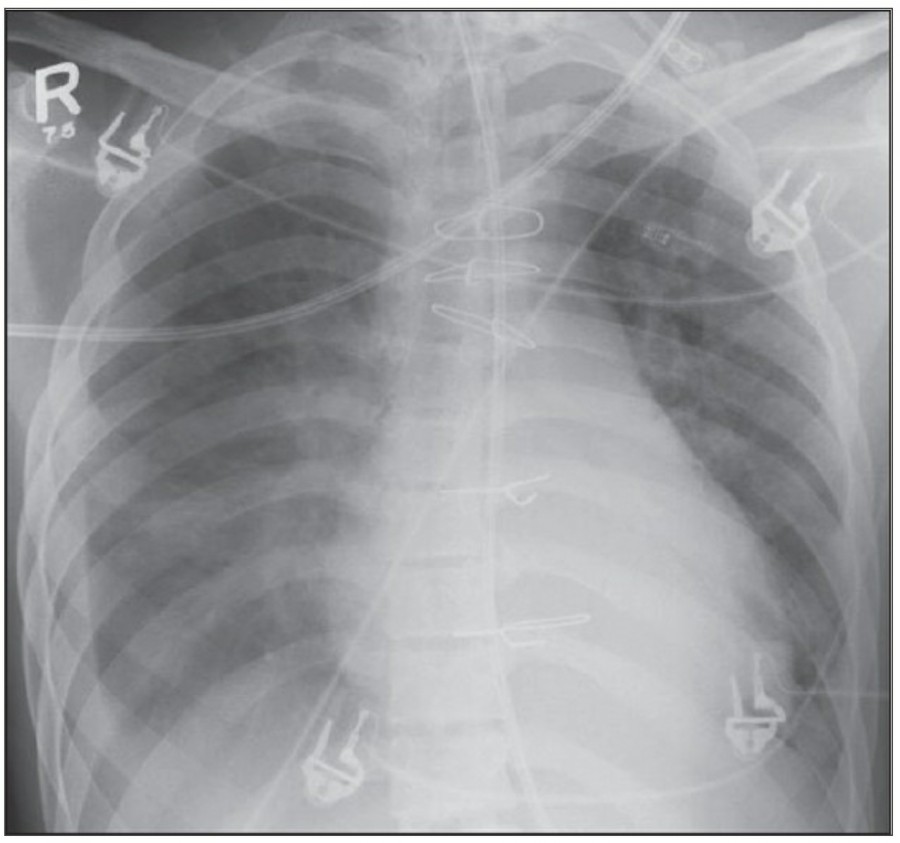

Pleural effusion

방사선 소견상 Pleural effusion은 환자 흉부의 dependent area에 고인다. Erect position에서 확인하기가 쉬운데, 폐의 base에 고임으로써 costophrenic angle blunting을 보이고 lower lobe vessel들의 흐리게 한다. Supine position에서는 확인이 더 어려운데, pleural fluid는 posterior basilar space에 고여서 폐 base 쪽으로 intensity가 증가하는 homogenous density를 보인다. 정상적인 bronchoalveolar marking은 이와 같은 veil-like density 안에서 확인 가능하다. Fluid 양이 늘어나면서 diaphragm의 윤곽이 흐릿해지고 costophrenic angle도 없어지는데, 이 costophrenic angle blunting이 없더라도 pleural space에 1L 정도의 pleural fluid가 있을 수 있다는 것을 기억해야 한다. 그 양이 더욱 늘어날 수록 fluid는 lung의 apex에서 pleural cap으로 나타날 수 있으며, 이는 supine position에서도 확인 가능하다. Pleural fluid는 lung의 medial side에 고일 수도 있으며 이는 mediastinum의 확장으로 보일 수도 있다.

적은 양의 pleural fluid는 꼼꼼히 확인하더라도 supine radiograph에서 놓칠 수 있는데, 만약 chest X ray에서 보이지 않지만 임상적으로 의심이 되는 경우에는 lateral decubitus film으로 확인해 볼 수 있다. Fluid는 dependent position에 고이므로 환자를 의심되는 방향으로 옆으로 눕혀야 한다. Lateral decubitus film은 적은 양의 pleural fluiid는 물론이고 loculated effusion과 free effusion을 확진하는 데도 도움이 된다. 특히 loculated effusion은 한 개 이상의 drain이 필요할 수 있으므로 pleural drainage를 고려할 때 특히 중요한 검사이다. 중환자에서 흔하게 나타나는 subplumonic effusion은 lung base에 존재하는 pleural effusion을 말하는데, chest X ray 상에서 raised hemidiaphragm with flattening and lateral displacement of the dome 형태로 나타나며, lateral decubitus film이 도움이 된다.

Loculated pleural effusion의 진단은 쉽지 않은데, 특히 fissure 안에 있을 때 어렵다. Loculted effusion이 minor fissure 안에 있고 right middle lobe atelectasis가 있다면 supine chest radiograph에서 감별이 어려운데, interlobular effusion은 biconvex edges와 homogenous density로 나타나고 minor fissure는 유지되는 반면, atelectasis는 concave margin과 inhomogenous density로 나타나며 right heart border와 minor fissure가 보이지 않게 된다. 이런 경우 erect lateral radiograph나 CT가 도움이 될 수 있다.